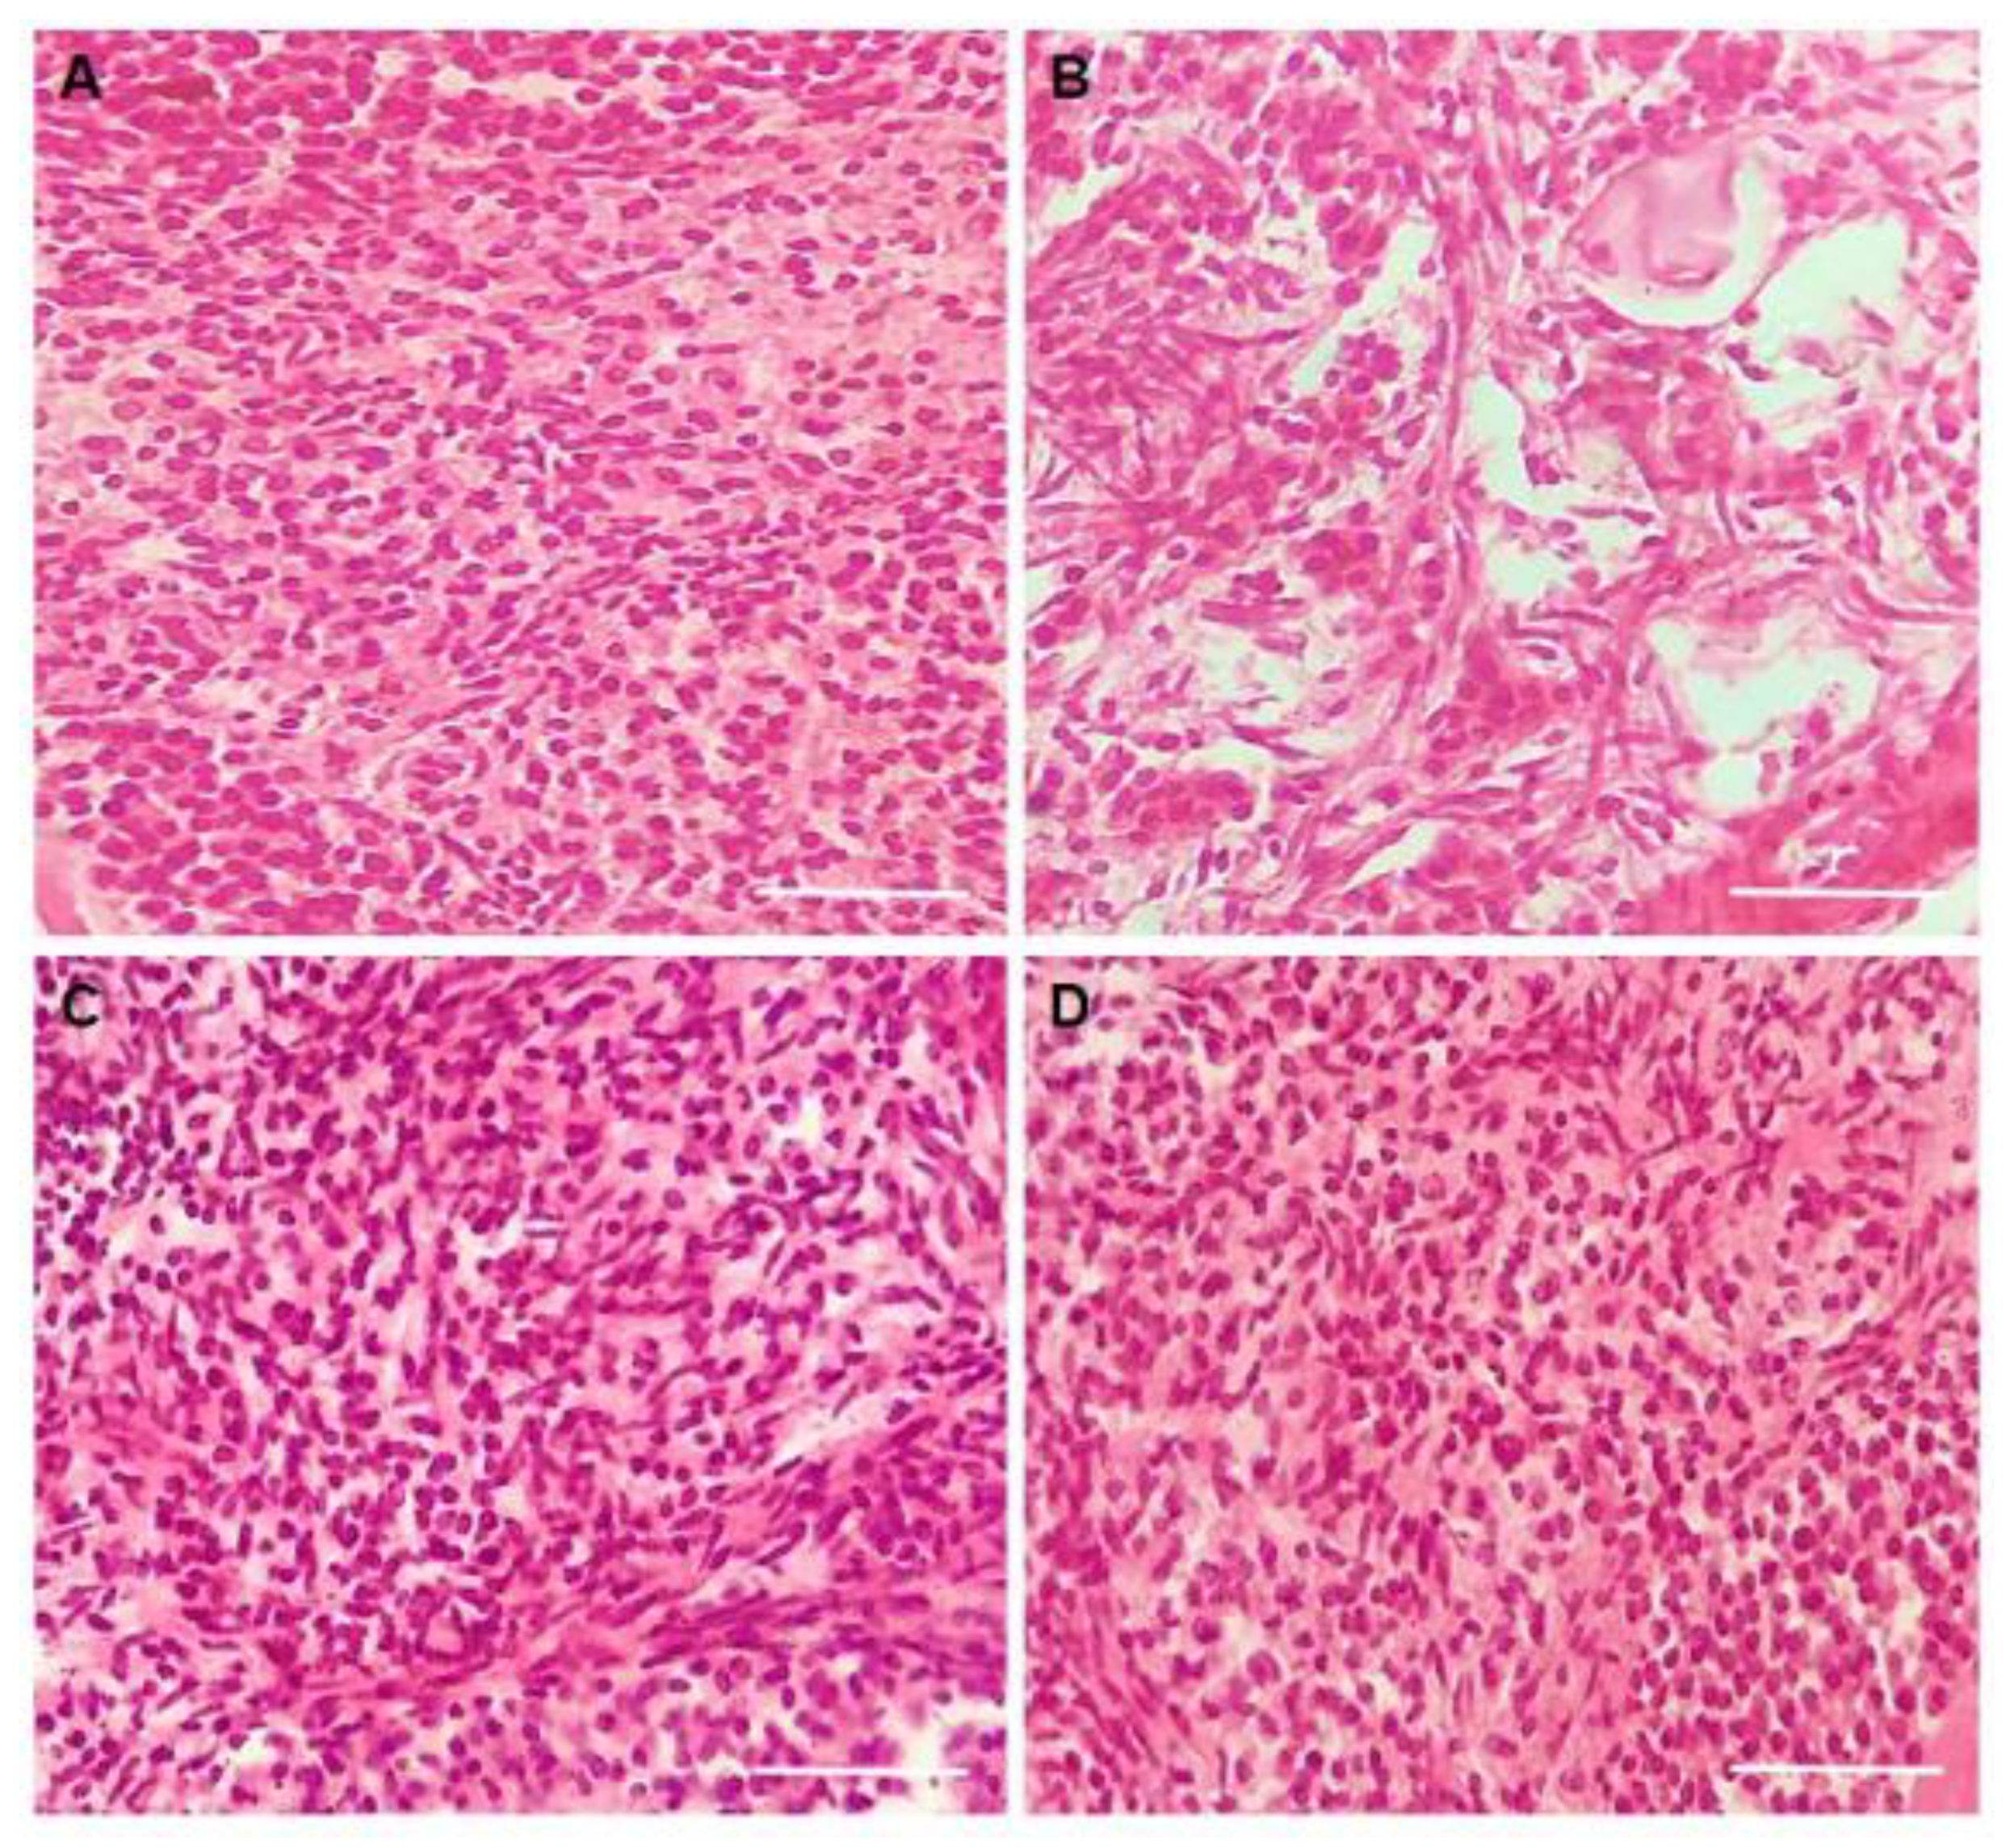

3.3. Experiment 2: Potential of CIMI to Reduce Damage Caused by DOXO on In Vitro Culture of Mouse Ovaries

3.6. Evaluation of Stromal Cells Density after In Vitro Culture of Mice Ovaries

3.7. Viability Assessment of Follicles after Culture